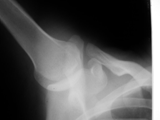

Fat pad sign-posterior-elbow

Fat pad sign-posterior-elbow